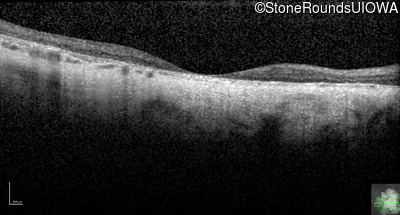

Age at visit: 43 years

OD OS